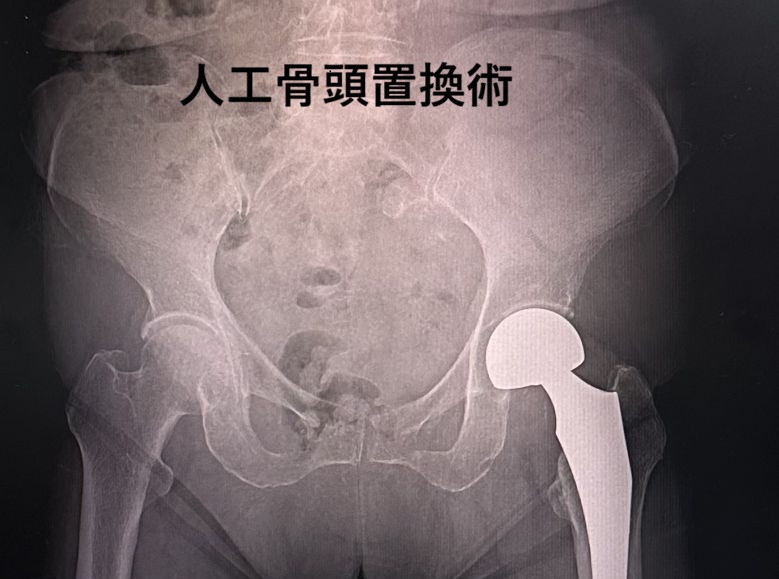

| 大腿骨近位部骨折 | |

| 大腿骨は解剖学的に近位部・骨幹部・遠位部に分かれます。さらに近位部は頚部・転子部・転子下に分かれます。したがって近位部骨折は大腿骨頚部骨折、大腿骨転子部骨折、大腿骨転子下骨折に分類されます。 大腿骨頸部骨折は関節内の骨折ですから内側骨折とも呼ばれています。一方、大腿骨転子部骨折や転子下骨折は関節外の骨折ですから外側骨折とも呼ばれています。骨粗鬆症を有する高齢者は些細な転倒や捻挫などで簡単に骨折されます。若年者は転落やスポーツ外傷などの強い外力で発生します。 大腿骨頚部骨折 大腿骨頸部骨折 (レントゲン所見)は大腿骨転子部骨折や転子下骨折に比べ骨癒合(骨のつき)がよくありません。何故なら内側骨折は関節内骨折(関節の袋の中の骨折)です。骨折を起こすと骨頭を栄養している血管も損傷され骨頭への血流が途絶え、後日、大腿骨頭壊死(骨頭が腐る状態)を起こすことががあります。また、骨癒合しても(骨がついても)後日、大腿骨頭壊死を発生することもありますので注意深い経過観察が必要です。 症状 症状は大腿骨の根元(股関節)の痛み、腫れ、運動障害、歩行障害を認めます。 診断 レントゲンで4つのStageに分類されます。 ■Stage1は不全骨折です。 ■Stage2は転位(ずれ)のない完全骨折です。 ■Stage3は軽度な転位を認める完全骨折です。 ■Stage4は高度な転位を認める完全骨折です。 Stageによって治療方針が決定されます。 治療 1)保存的治療(手術しない方法) 長期間の安静が必要となります。高齢者が長期間安静を強いられると、全身状態の悪化や様々な合併症を併発します。そのため保存的治療の適応は極めて限定されます。 2)手術的治療 手術は年齢、骨折のタイプ、併存症を考慮して検討されます。術式は骨接合術、人工骨頭置換術です。術後は早期に股のストレッチング、股の筋力強化訓練、歩行訓練、バランス訓練などの運動器リハビリテーションを行います。 大腿骨転子部骨折・大腿骨転子下骨折 大腿骨転子部骨折・大転子転子下骨折は関節の袋の外の骨折ですから骨癒合(骨のつき)は良好です。全身状態に問題がなければ骨接合術が行われます。術後は内側骨折と同様に運動器リハビリテーションが行われます。